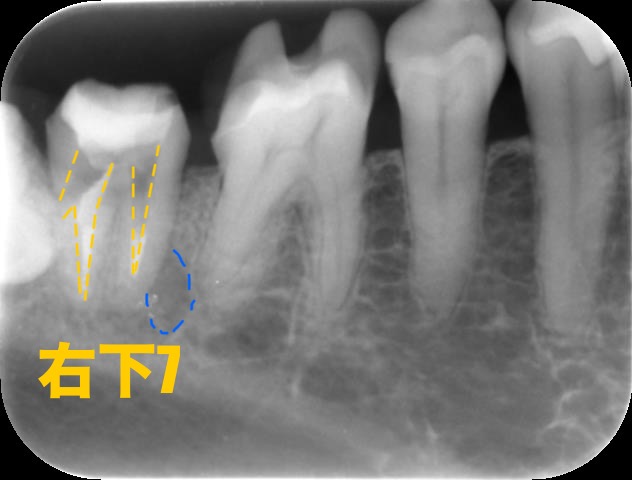

次に治療前のデンタル、CT写真をご覧下さい。

黄色い部分が治療によって拡大された根管なのですが、左側に1部大きく斜めに空けられてしまっている部分があるのがわかると思います。

これはパーフォレーションと言って歯の根管の壁に穴が空いてしまうことを言います。

原因としては間違った方向に器具を動かしてしまうことで起こります。

歯の根っこの周囲には「歯根膜」という血管を豊富に含んだ組織が存在します。歯根部にパーフォレーションを起こすとまずは空いた穴より出血が見られます。そこに細菌感染が起こることで痛みが出たり歯茎が腫れることがあります。また痛みなどが出ずに経過が長期になると、周囲の骨が溶けてしまいます。

青い部分が溶けた骨の部分でレントゲンでは黒く写ります。

大きく空き過ぎて修復不可能な場合や修復できたとしてもその後すぐに歯が壊れてしまう可能性が高い場合は残念ながら「抜歯」という診断となります。

ですが今回は回復の見込みがあると判断し、パーフォレーションリペアを行います。